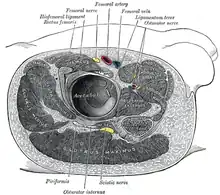

Le muscle piriforme a une forme de poire. Il se dirige en dehors, en avant et en bas.

La face postérieure du muscle repose contre le sacrum. La face antérieure du muscle est liée au rectum (surtout du côté gauche du corps) et au plexus sacré[1].

traverse la grande incisure ischiatique qu'il partage en deux espaces : supra-piriforme et sous-piriforme.

Le muscle piriforme fait partie des muscles qui ferment l'enceinte du bassin pour séparer les viscères pelviens de la racine des membres inférieurs.

Le muscle piriforme est un repère très important dans la région fessière. En traversant la grande incisure ischiatique, il la divise en une partie inférieure et une partie supérieure, déterminant ainsi la terminologie supérieure (au-dessus du muscle) et inférieure (en dessous du muscle) pour les nerfs et vaisseaux de la région.

Du fait de la proximité du nerf sciatique avec le muscle piriforme, voire son passage à travers ce muscle, sa sollicitation excessive peut entraîner une inflammation du nerf. Son surmenage peut advenir dans certains sports (course à pied, cyclisme, ...) ou survenir lors d'une mauvaise posture récurrente (mauvais siège et mauvais appui fessier). Ceci peut avoir pour conséquence l'apparition d'un syndrome de type sciatique appelé syndrome du piriforme.

Fémur droit.Vue antérieure. Structures entourant la hanche droite.

Structures entourant la hanche droite. Les muscles du bassin.